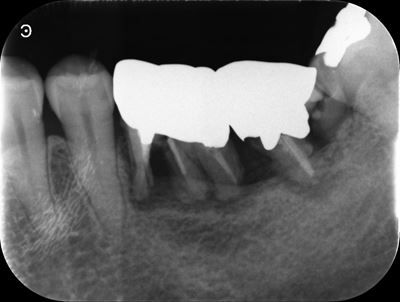

左下6番X線画像

移植歯レプリカの試適(移植床の適合確認):症例1-2

X線にて移植床形成量を確認